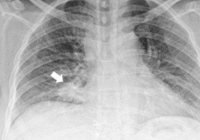

Ung thư phổi thường gây khàn giọng và khó thở cũng như cảm giác thắt chặt ở cổ họng. Điều này càng dễ nhận ra hơn vào buổi sáng sớm, khi mà cơ thể vừa mất nước sau một đêm ngủ dài. Đương nhiên, ban đêm khi nhiệt độ giảm xuống triệu chứng khàn giọng cũng có thể rõ ràng hơn.

Cảm giác khó thở do khối u phổi cũng thường xảy ra hoặc nặng hơn vào mỗi sáng ngủ dậy. Thay đổi tư thế nằm sang ngồi, đứng, vận động gắng sức nhiều hơn cũng được cho là 1 nguyên nhân dẫn tới tình trạng này.

Sự khác biệt của khàn tiếng, khó thở do ung thư phổi vào buổi sáng là nó kèm theo sự mệt mỏi dai dẳng dù ngủ đủ giấc. Có thể đi cùng cảm giác tức ngực, chóng mặt, cả người yếu ớt khó chịu như thiếu dưỡng khí. Sau một lúc, các triệu chứng này có thể tự thuyên giảm đáng kể nhưng sẽ lặp lại vào sáng hôm sau.